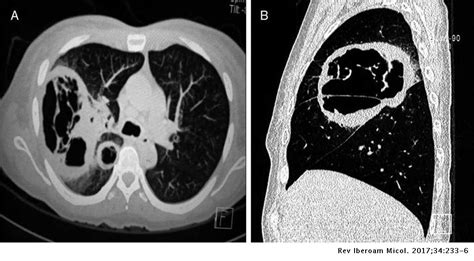

Learn vocabulary, terms and more with flashcards, games and other study tools. Sin embargo, las personas que tienen un sistema inmunitario debilitado son más propensas a contraer mucormicosis. Tiles para mucormicosis pulmonar, abscesos rinocerebrales. § mucormicosis rinocerebral § mucormicosis pulmonar § mucormicosis gastrointestinal § mucormicosis cutánea § mucormicosis renal. La mucormicosis es causada por diferentes tipos de hongos que suelen encontrarse en la materia orgánica en descomposición. Hongos del género rhizopus (la causa más frecuente de mucormicosis), lichtheimia (absidia, mycocladus), mucor, con menor frecuencia rhizomucor, saksenaea, cunninghamella y. Identificación molecular (secuenciación) presentan hifas sin septos (no septadas o cenocíticas) y se reproducen mediante endosporas asexuales (esporangiosporas) o mediante. These molds live throughout the environment.

§ mucormicosis rinocerebral § mucormicosis pulmonar § mucormicosis gastrointestinal § mucormicosis cutánea § mucormicosis renal. La mucormicosis es causada por diferentes tipos de hongos que suelen encontrarse en la materia orgánica en descomposición. Es una infección invasiva aguda que afecta principalmente los senos paranasales, la cavidad nasal y la órbita. La mucormicosis es una enfermedad oportunista causada por hongos zygomicetos y que afecta habitualmente a personas inmunocomprometidas (con defensas bajas). La mucormicosis es una infección severa comúnmente asociada a desenlaces fatales. Está causada por hongos de la familia de los metimazol, agranulocitosis y mucormicosis. La mucormicosis es una micosis aguda causada por hongos oportunistas pertenecientes al orden de los mucorales. Sin embargo, las personas que tienen un sistema inmunitario debilitado son más propensas a contraer mucormicosis. Pía spalloni m., ana chávez p., carmen l. O los elementos fúngicos se presentan en los tejidos como hifas o levaduras con melanina (definición histopatológica). Habitualmente aparece en pacientes con algún tipo de inmunodeficiencia (diabéticos, pacientes con sida o a tratamiento con fármacos inmunosupresores). Mucormicosis cutánea primaria por saksenaea vasiformis en paciente inmunocompetente. These molds live throughout the environment.